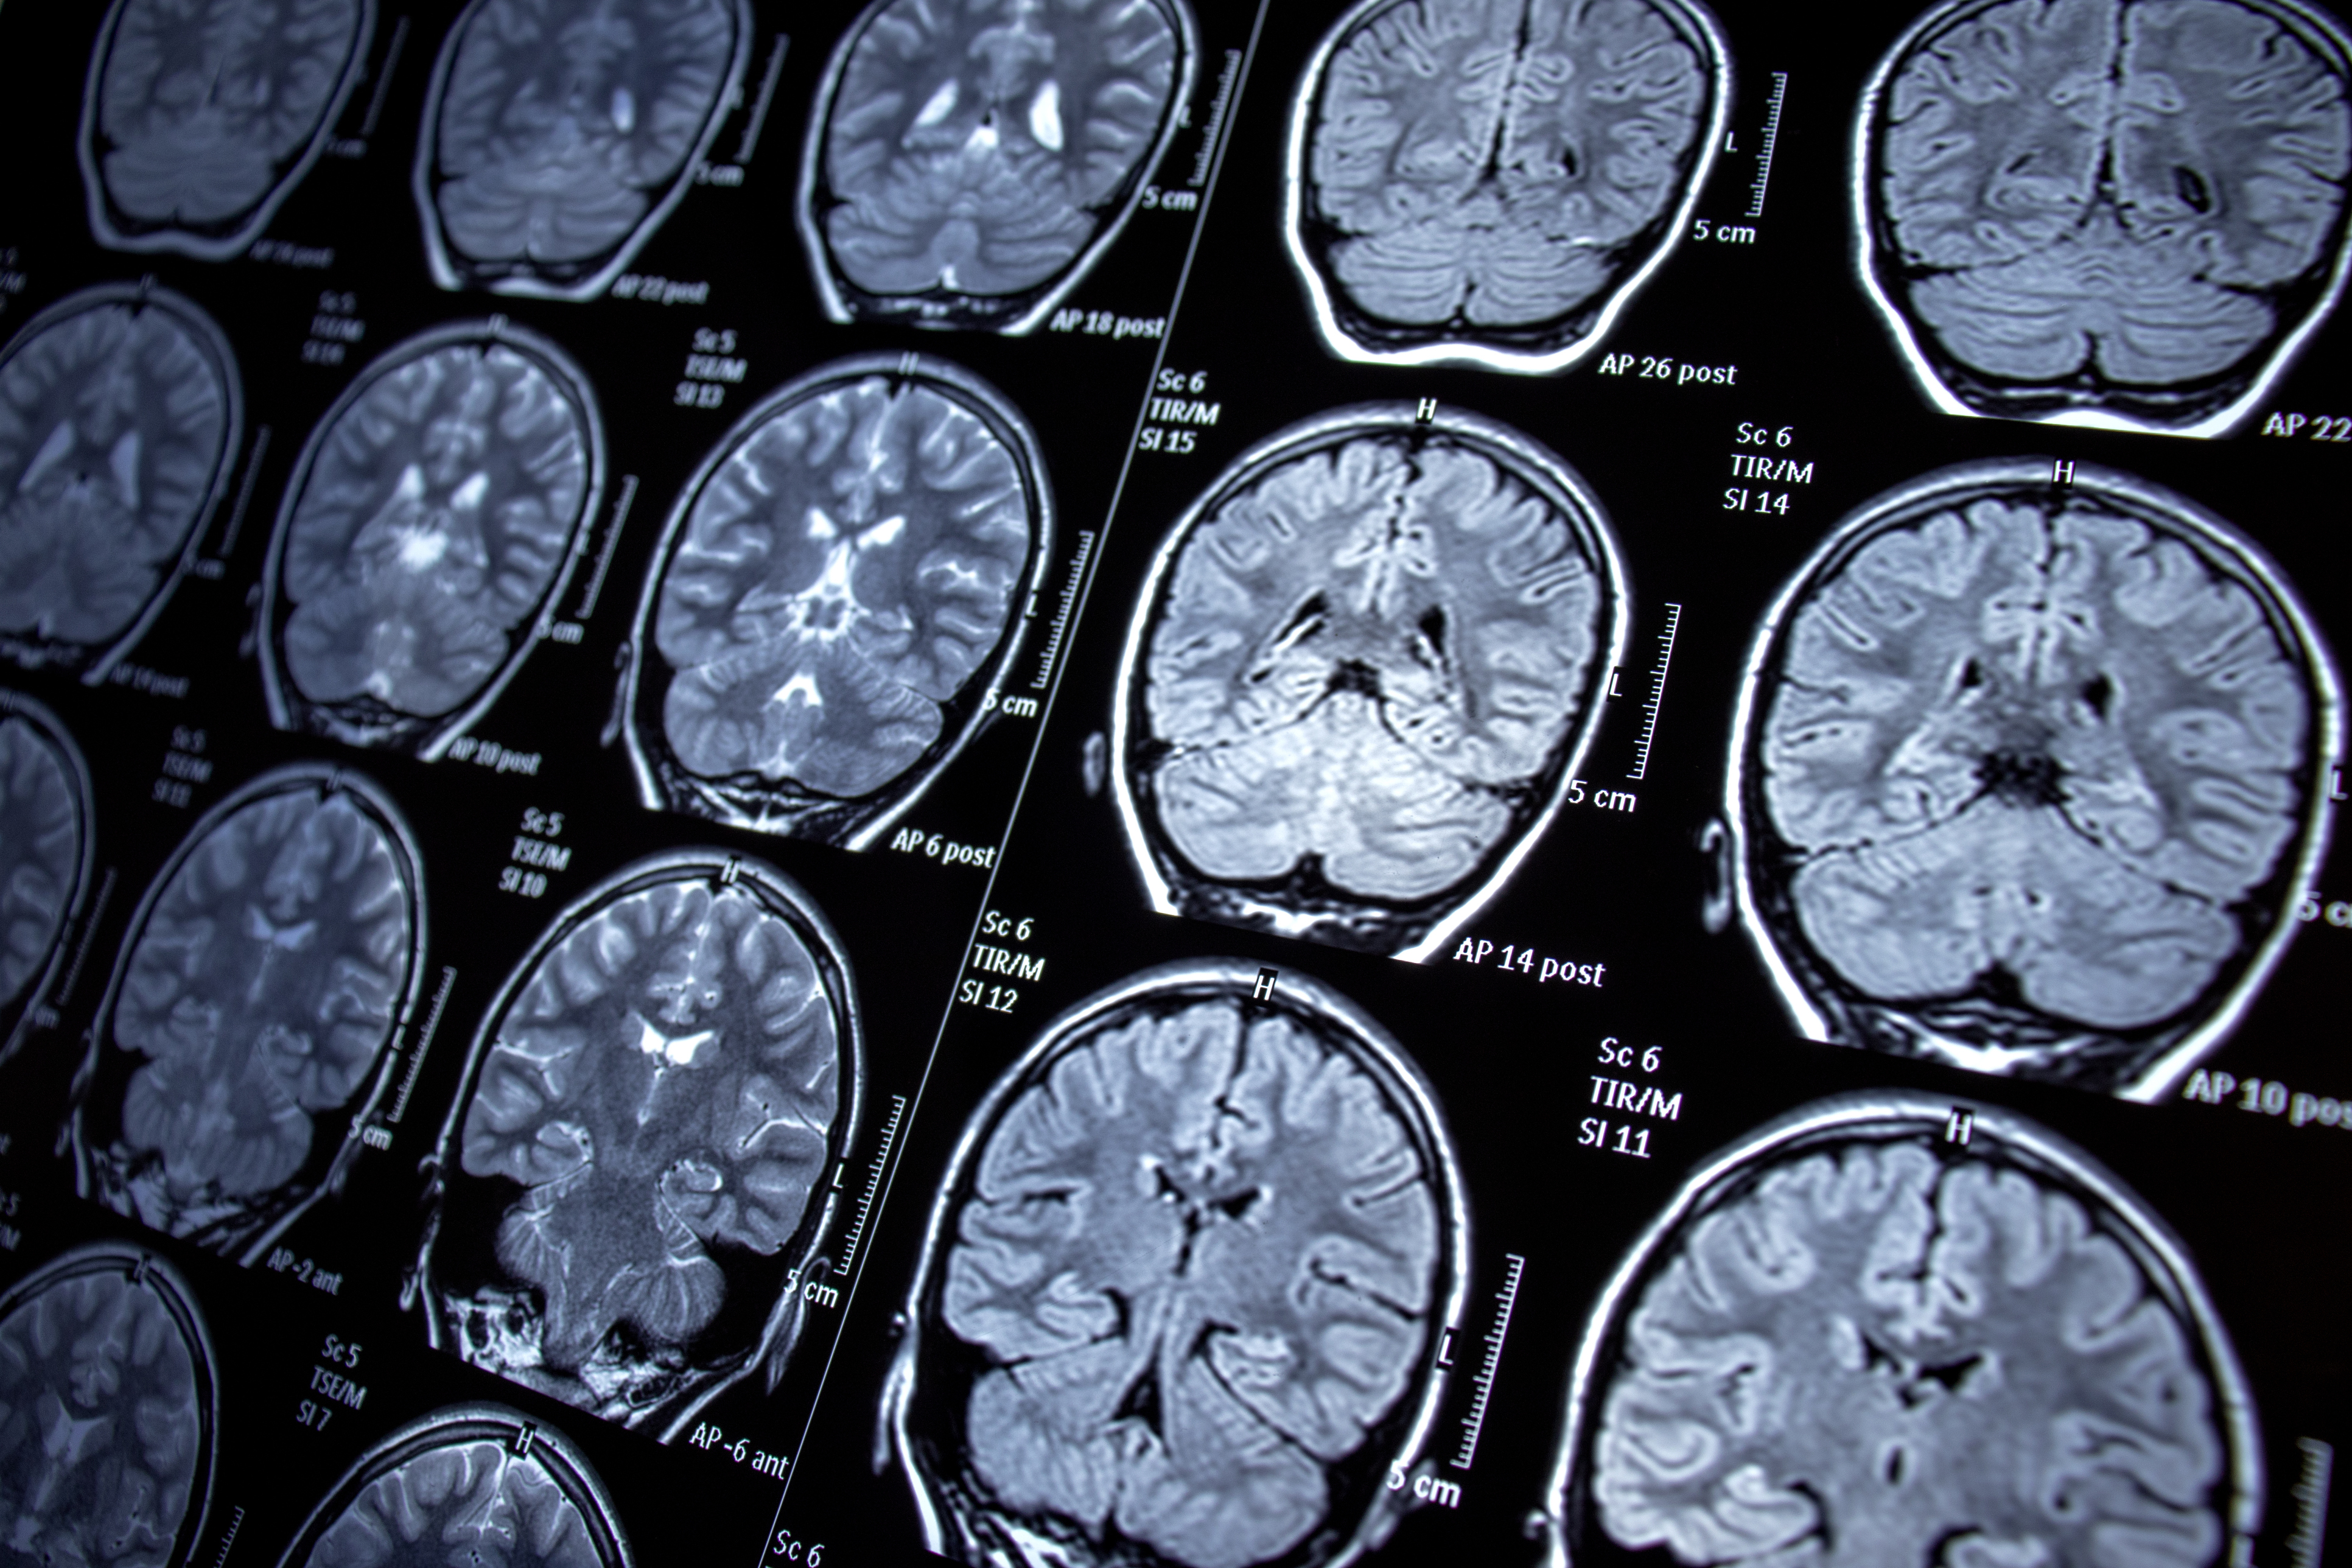

據英國媒體《The Mirror》報導指,蘇格蘭24歲女護士Fern Cameron於去年1月開始,她在工作期間精神狀態變得異常,經常失平衡站不穩,亦時常變得暴躁,惟她一直沒有理會。直至她的視力看到有「重影」症狀,才驚覺事情不太對勁,於是接受進行磁力共振臂(MRI)檢查發現,Fern的腦部長了一顆巨大的星狀細胞瘤(astrocytoma)。